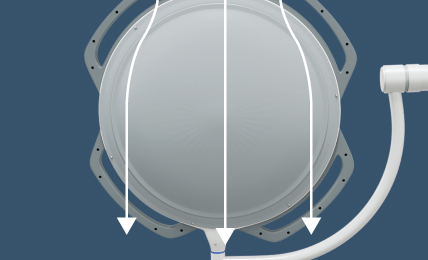

Endo Mode

500 mm